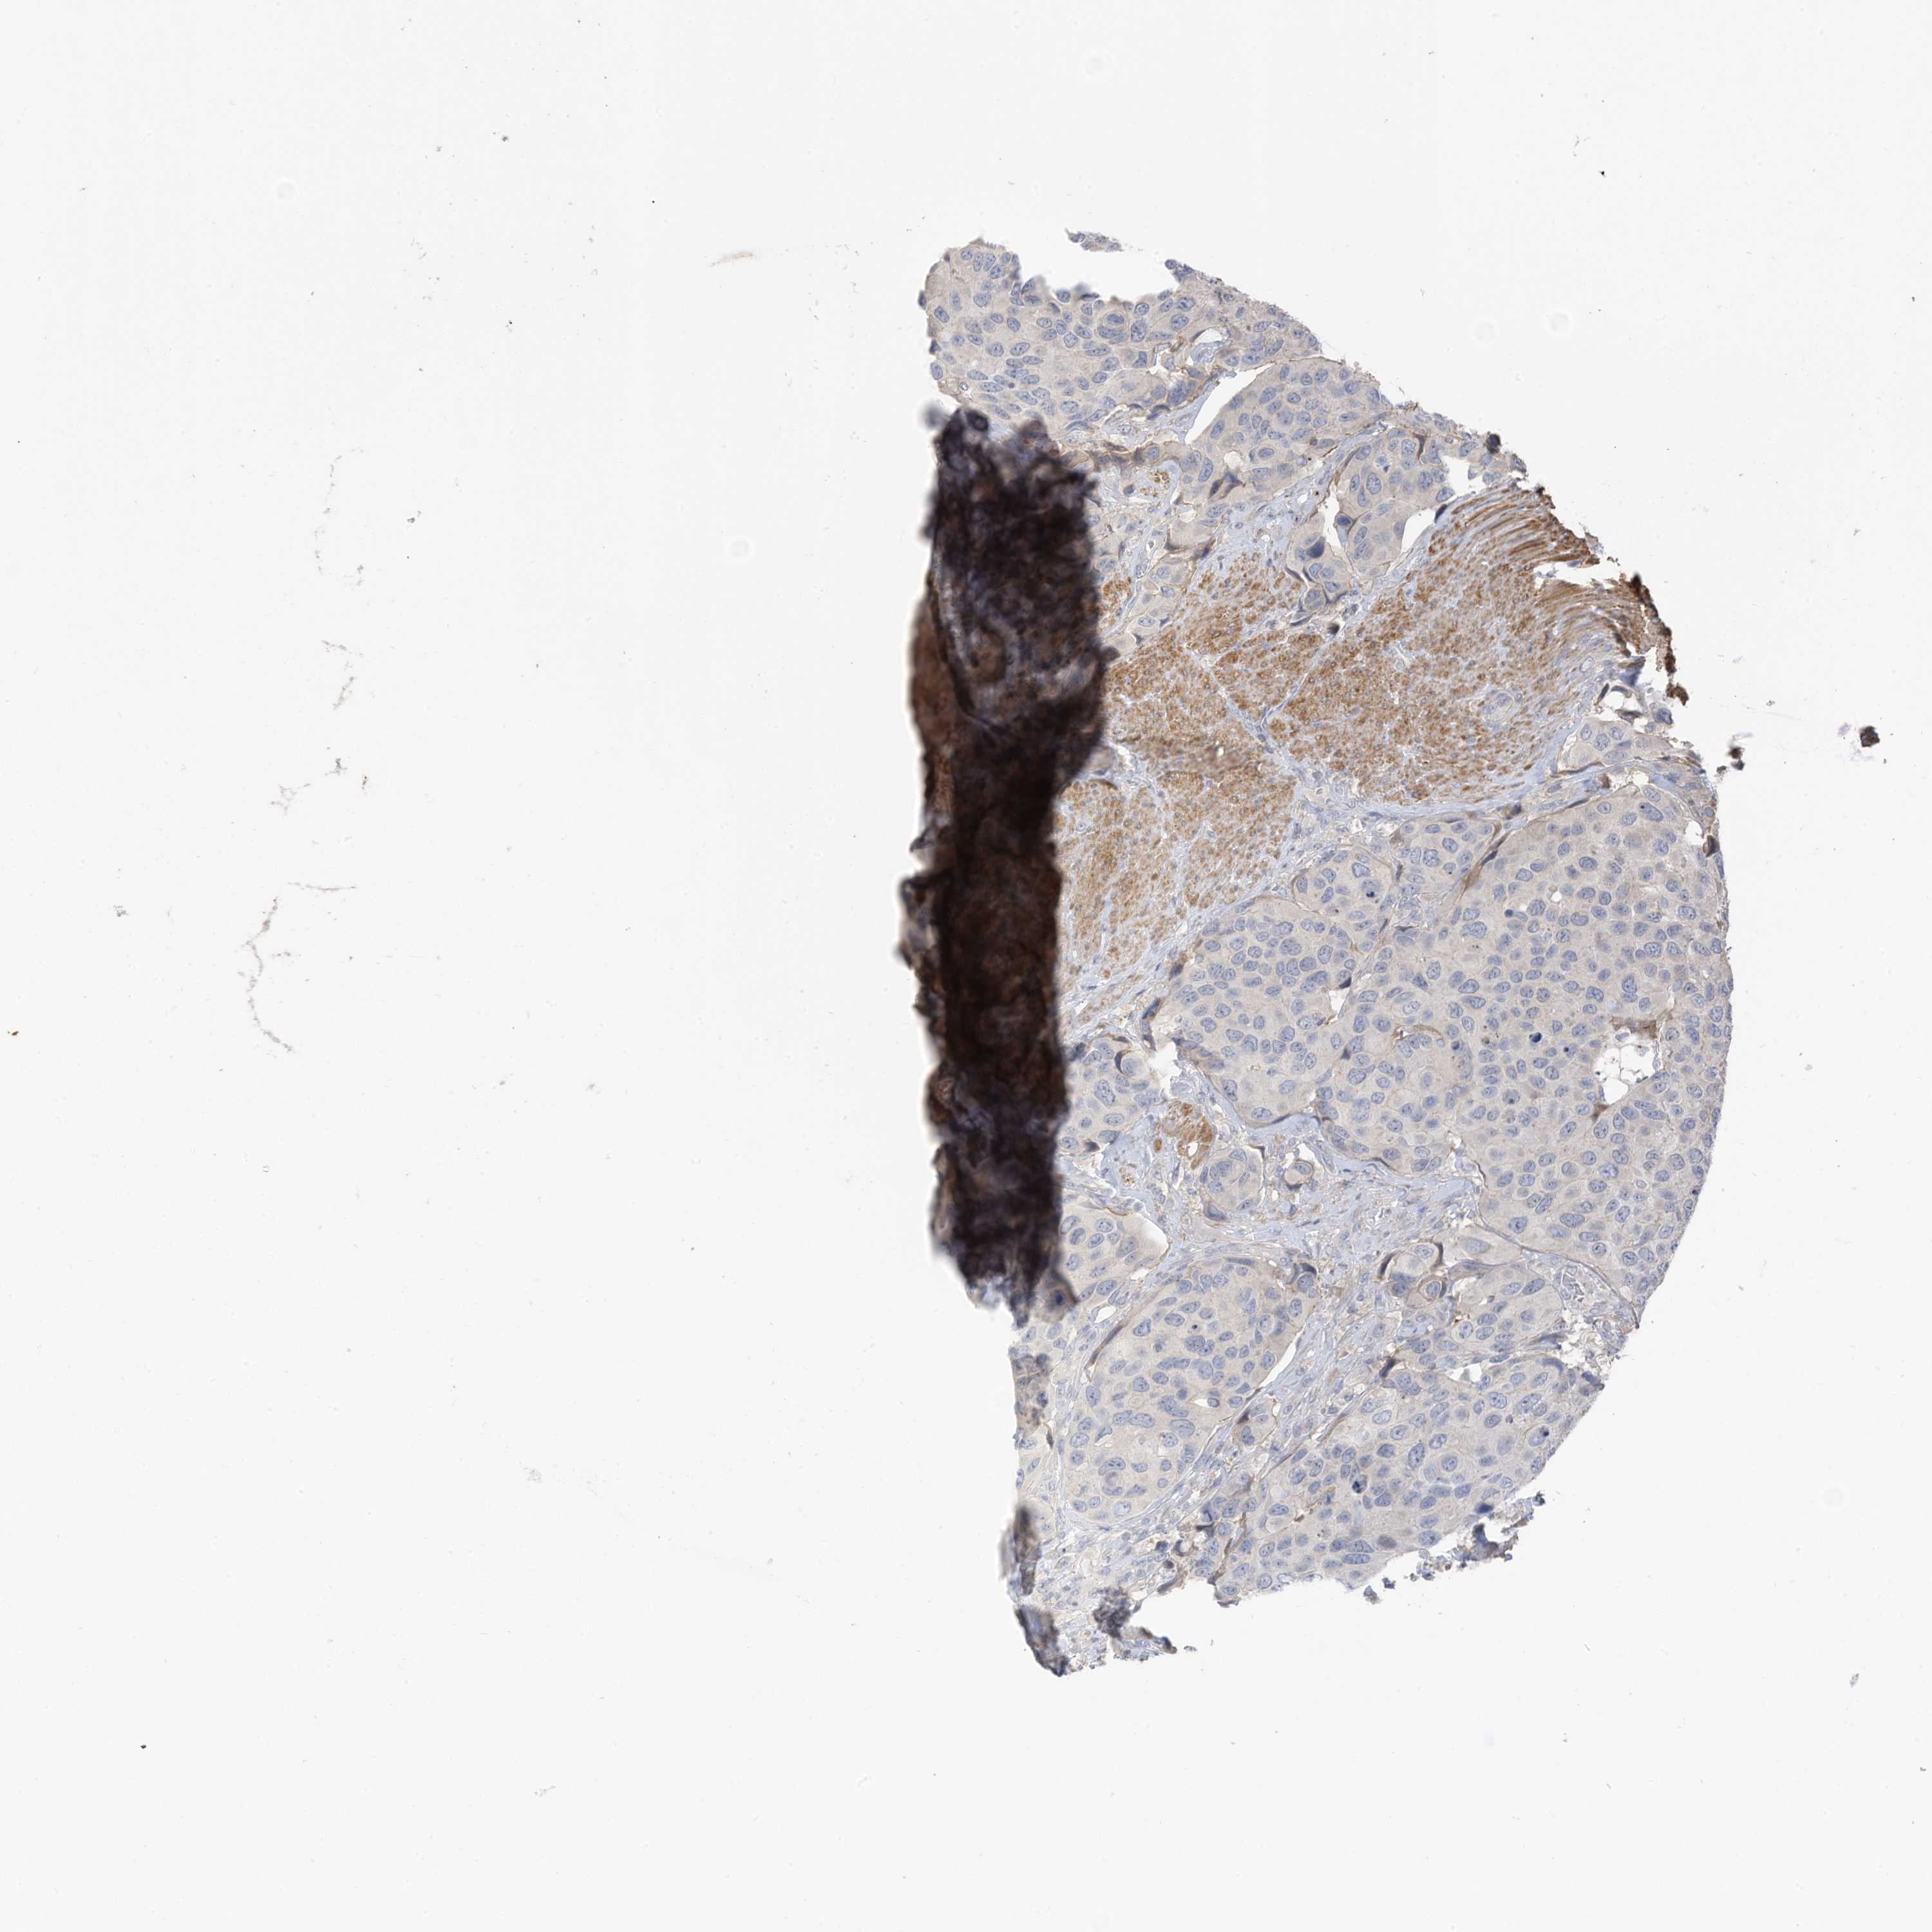

UROTHELIAL CANCER - Protein expressioni

A mouse-over function shows sample information and annotation data. Click on an image to view it in a full screen mode. Samples can be filtered based on level of antibody staining by selecting one or several of the following categories: high, medium, low and not detected. The assay and annotation is described here.

Note that samples used for immunohistochemistry by the Human Protein Atlas do not correspond to samples in the TCGA dataset.

Antibody stainingi

Antibody staining in the annotated cell types in the current human tissue is reported as not detected, low, medium, or high, based on conventional immunohistochemistry profiling in selected tissues. This score is based on the combination of the staining intensity and fraction of stained cells.

Each image is clickable and will lead to virtual microscopy that enables deeper exploration of all samples and also displays staining intensity scores, fraction scores and subcellular localization as well as patient and tissue information for each sample.

Antibody HPA022994

Antibody HPA023065

Urothelial carcinoma, High grade

Urothelial carcinoma, Low grade